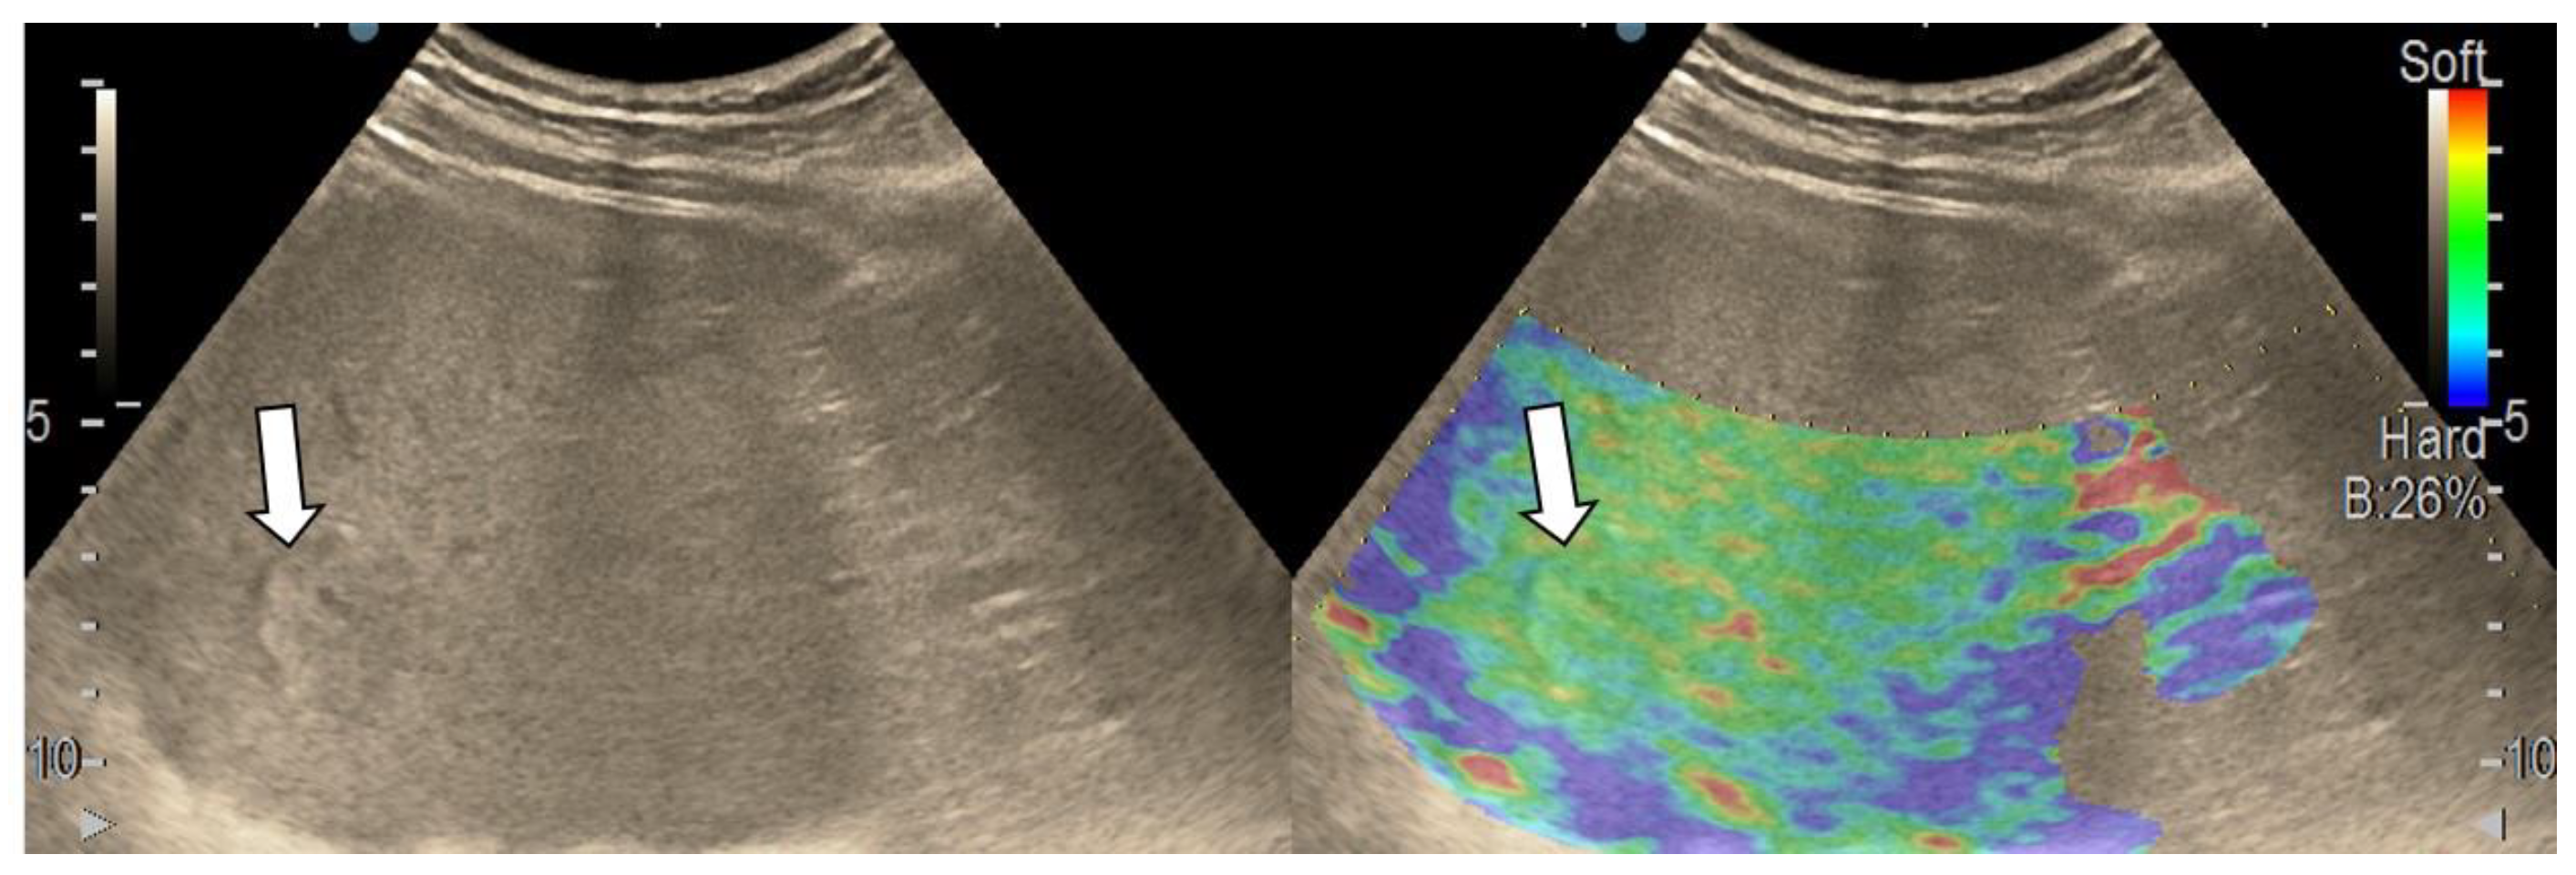

3.4. Real-Time Tissue Elastography

| Elasticity Type | Color Code |

|---|---|

| Type “a” | Homogenously green |

| Type “b” | Mosaic pattern with dominant green areas |

| Type “c” | Mosaic pattern with dominant blue areas |

| Type “d” | Homogenously light blue |

| Type “e” | Homogenously dark blue |

| RTE | Liver Adenoma | HMG | FNH | Complicated Liver Cyst | HCC | iCCA | Liver Metastases | Liver Lymphoma |

|---|---|---|---|---|---|---|---|---|

| Type “a” | 3 | 1 | ||||||

| Type “b” | 1 | 1 | 10 | 3 | 1 | |||

| Type “c” | 1 | 24 | 3 | 6 | ||||

| Type “d” | 1 | |||||||

| Type “e” | 5 | 3 | 1 |